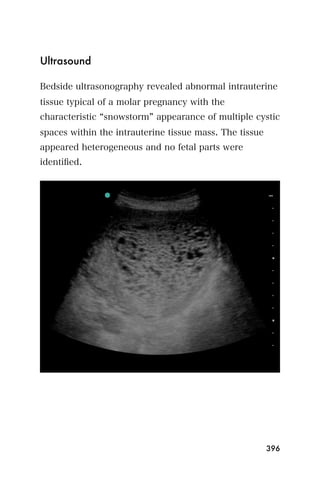

center that is the endometrium.

Figure 3. The bladder (*) and empty uterus (arrow)

An empty uterus may cause the clinician to worry about

an ectopic pregnancy. A ruptured ectopic pregnancy

blood may extend into the abdomen, so it is important

107

to look for blood within the abdomen as well as the

pelvis. The sonographer can begin imaging the area

between the liver and the kidney on the mother s right

side. This is the same window that is used to look for